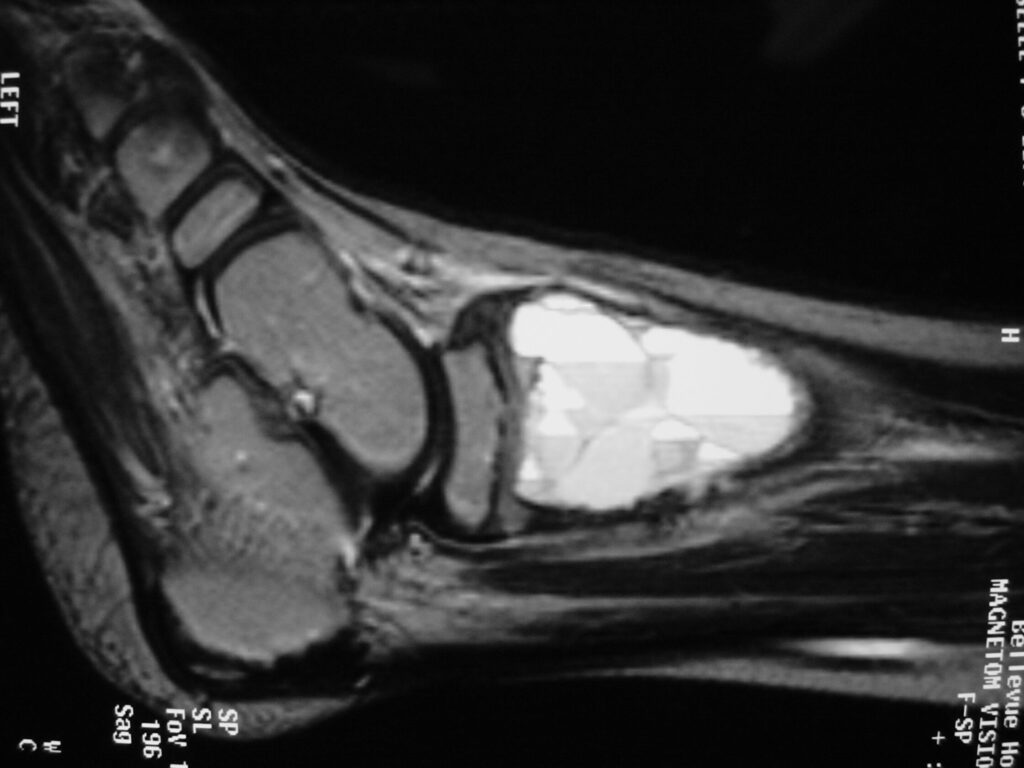

Fig 2 a-e. MRI of an ABC of Distal Tibia: Fig 2 a-c: geographic cystic expansile lesion with fluid-fluid levels. The fluid-fluid levels are caused by bleeding into the cavities. The blood collects and the degredation products settle to the gravity dependent areas of the cavities. This shows up as fluid-fluid levels on the MRI. Fig 2 d,e: This is a gadolinium enhanced MRI of the ABC of the distal tibia. There is peripheral and septal enhancement indication cyst formation. The contrast outlines the cystic cavities but does not enter into the center

Fig 2b: Sagittal T2 weighted MRI of and ABC

MRI

- Geographic well circumscribed

- High signal on T2 weighted MRI images

- Fluid/Fluid level (T2) are highly characteristic